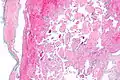

Intravascular papillary endothelial hyperplasia

Intravascular papillary endothelial hyperplasia is a rare, benign tumor. It may mimic an angiosarcoma, with lesions that are red or purplish 5-mm to 5-cm papules and deep nodules on the head, neck, or upper extremities.[1][2]: 592

Histopathology Images